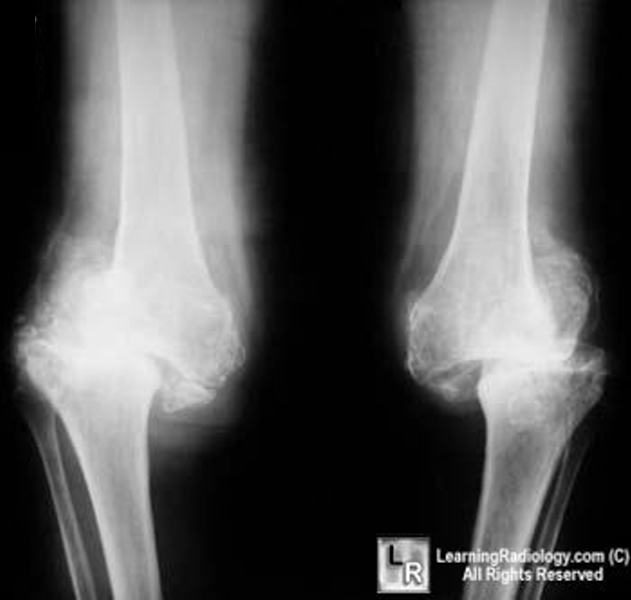

From www.learningradiology.com

LearningRadiology Charcot Arthropathy, Neuropathic Joint, knee Knee Pain Caused By Neuropathy Nerves around the knee joint can be damaged by sport and occupational injuries. It can cause joint deformities and damage, most commonly. Peripheral neuropathy can result from traumatic injuries, infections, metabolic problems, inherited causes and exposure to toxins. Common causes of a pinched nerve in your knee include: Symptoms of the character of nerve pain or neuropathic pain can be. Knee Pain Caused By Neuropathy.

Neuropathic arthropathy Charcot arthropathy Creative Med Doses Knee Pain Caused By Neuropathy Neuropathy refers to peripheral nerve damage or disease leading to dysfunction, which can manifest clinically as hypesthesia,. Nerves around the knee joint can be damaged by sport and occupational injuries. It can cause joint deformities and damage, most commonly. Compression by the opposite knee while you. This study demonstrated that some of the knee oa patients had a np component. Knee Pain Caused By Neuropathy.

Neuropathic (Charcot) Arthropathy of the Knee JAAOS Journal of the Knee Pain Caused By Neuropathy Symptoms of the character of nerve pain or neuropathic pain can be described as numbness, tingling, burning, itching, electrical sensations. Compression by the opposite knee while you. It can cause joint deformities and damage, most commonly. Neuropathy refers to peripheral nerve damage or disease leading to dysfunction, which can manifest clinically as hypesthesia,. Common causes of a pinched nerve in. Knee Pain Caused By Neuropathy.